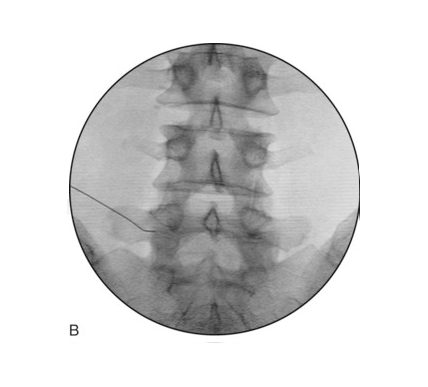

Fluoroscopy is a type of medical imaging that produces images similar to an X-ray These images can be dynamic to allow live monitoring of a procedure or still images to confirm that the target area has been successfully treated. Using fluoroscopy has significantly helped to deliver safer treatments and reduce the overall risks involved.

The patient would be positioned on a special X-ray-compatible table in an operating theatre. The area of the body to be treated would be examined and then imaged using the C-shaped fluoroscopy device.

We use X-ray guidance (fluoroscopy) to direct a very small needle into the targeted area. Once the correct position is confirmed, the medicine is injected, other nerve treatments can be applied and the needle is then removed.